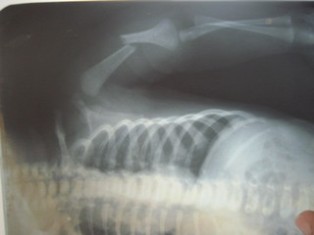

Scoliosis and Kyphosis